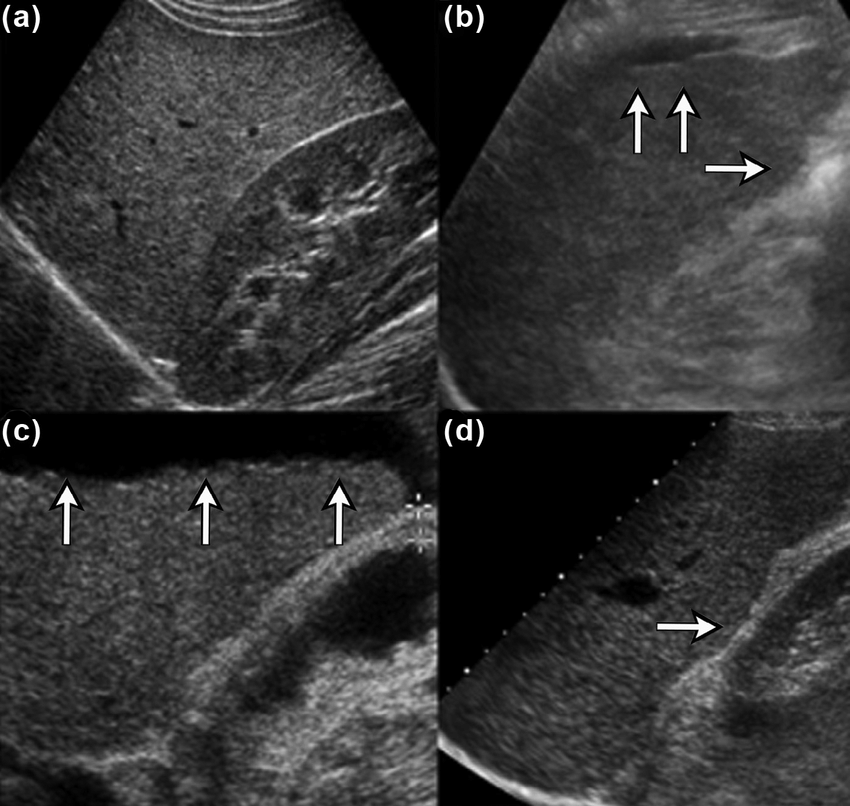

Problem: Da li je nodularnost konture jetre povezana sa konzumiranjem alkohola?

Standardan način prikazivanja kategorijalnih podataka je preko tabele kontigencije.

Predstavlja broj (ili proporciju) opservacija koje pripadaju svim mogućim kombinacijama kategorija.

| Nodularne promene | Alkohol: Da | Alkohol: Ne |

|---|---|---|

| Ne | 16 | 79 |

| Da | 10 | 13 |

Pearson's Chi-squared test

data: nodularnost_dat

X-squared = 7.6474, df = 1, p-value = 0.005685

“Postoji statistički značajna asocijacija između nodularne konture jetre i konzumiranja alkohola.”